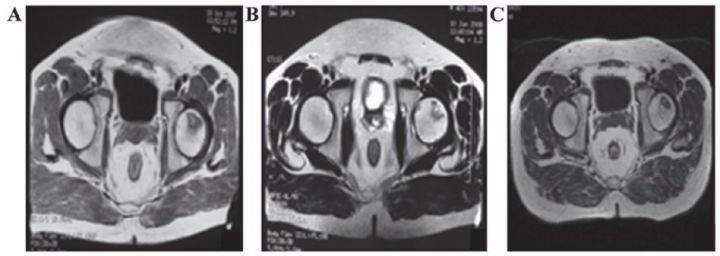

吉林省組織工程重點實驗室劉穎教授 、首都醫科大學宣武醫院谷涌泉主任等,對9位骨循環協會評級為II-IIIa級的股骨頭壞死患者經大腿動脈輸注臍帶間充質干細胞后,患者的紅細胞、血小板、血氧轉運指數明顯改善。MRI檢測顯示24個月后股骨頭壞死區域體積顯著減少。